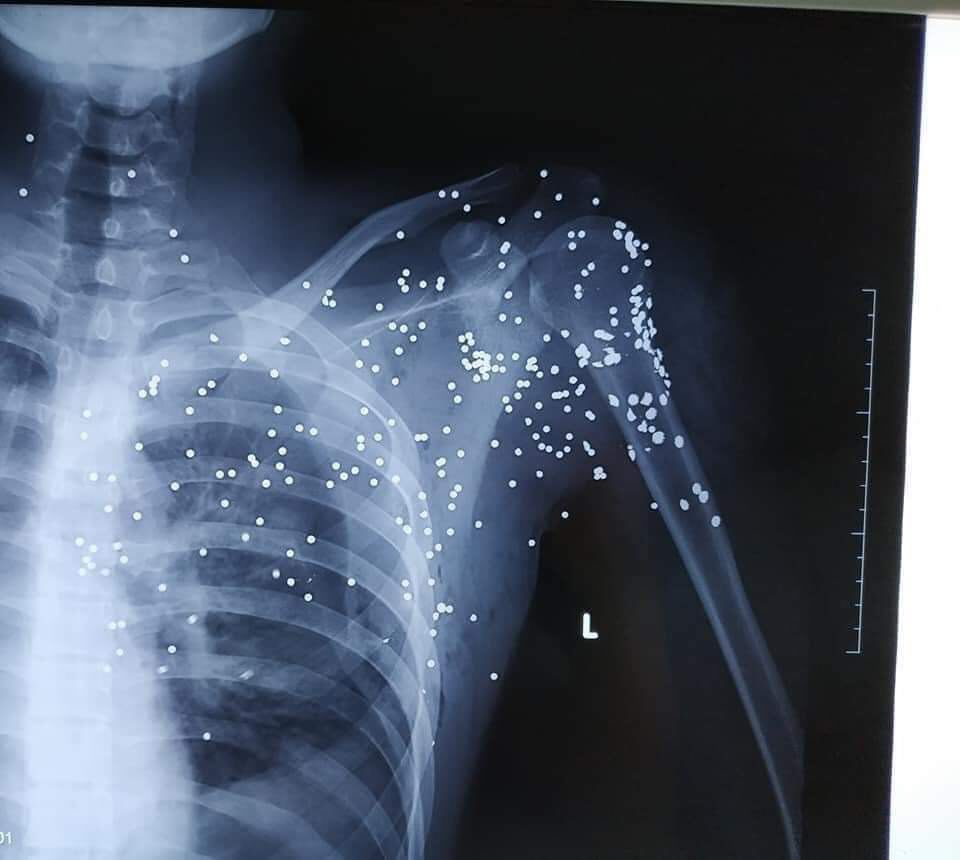

Những vết đạn chi chít trên cơ thể nạn nhân.

Như VTC News đưa tin, khoảng 20h ngày 23/11, anh B.H.H (19 tuổi, trú tại xã Bình Minh, huyện Kiến Xương) từ xe ô tô xuống quán nước gần Trạm thu phí Thanh Nê (nằm trên đường 39B thuộc địa phận xã Bình Minh) thì bị Bùi Xuân Đại mở cửa xe khách, dùng súng hoa cải bắn.

Sau đó, kẻ này rời đi. Anh H. được gia đình và người dân đưa đi cấp cứu tại Bệnh viện Đa khoa tỉnh Thái Bình trong tình trạng đa chấn thương, mất nhiều máu.

Sau khi được sơ cứu, các bác sĩ chuyển bệnh nhân lên Bệnh viện Hữu nghị Việt Đức (Hà Nội) tiếp tục điều trị.